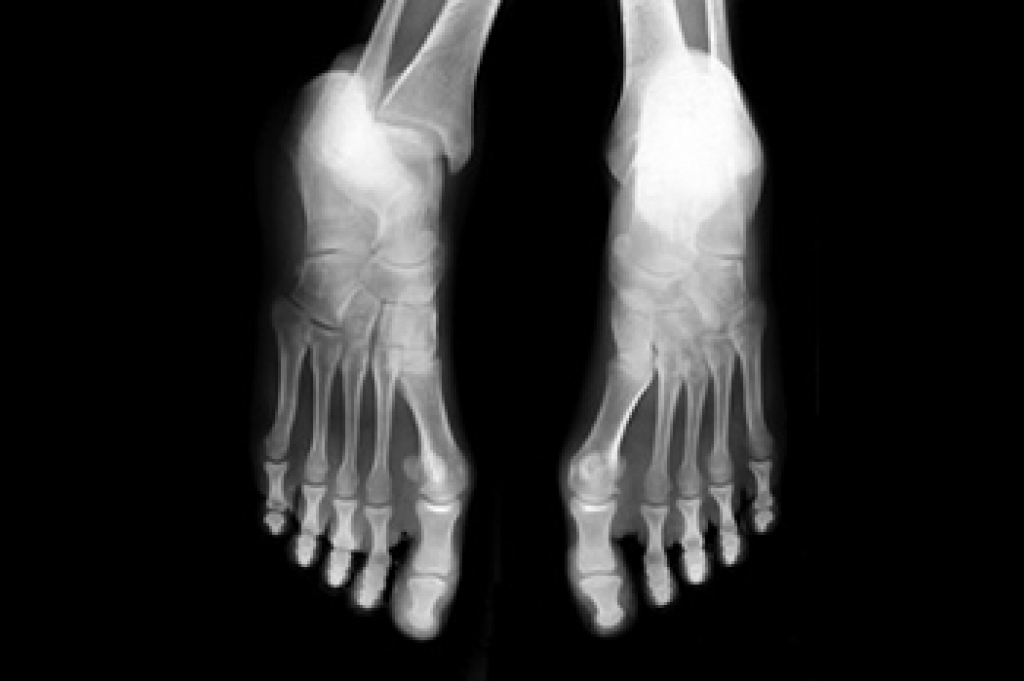

A plantar fibroma will not disappear without treatment, but it can get smaller and be a non-issue. If pain persists, a podiatrist examines the foot and when the arch of the foot is pressed, pain can be felt down to the toes. An MRI or biopsy might be performed to help diagnose or evaluate the plantar fibroma. The following non-surgical options are generally enough to reduce the size and pain of these nodules: